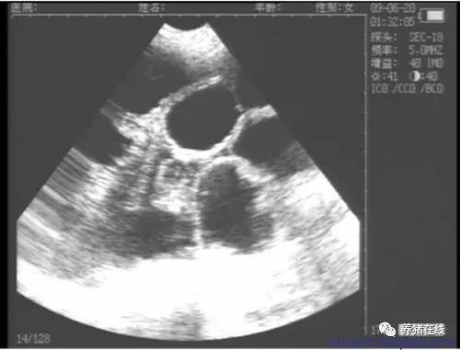

導(dǎo)讀 為了最大化豬場的生產(chǎn)效益,我們要盡量縮減母豬的非生產(chǎn)天數(shù),提高母豬的利用率。 配種后的母豬要度過兩大關(guān)卡:返情和受孕。 母豬一旦返情,我們就要多飼喂一個(gè)情期,增加了非生產(chǎn)天數(shù),提高了養(yǎng)殖成本。而配種母豬如果沒有檢查受孕與否,萬一到了臨產(chǎn)前才發(fā)現(xiàn)母豬空懷,那么我們的成本就要增加114天左右的費(fèi)用,比起返情的成本要大得多。 所以,我們不僅要做好母豬的返情檢查工作,更要做好母豬的受孕檢查。 母豬返情檢查 一般來說,母豬的發(fā)情周期是21天,但我們的返情檢查在配種后17、18天就開始了。 母豬返情檢查的時(shí)間宜早不宜晚,這樣做的目的是防止有的母豬發(fā)情周期短,返情不能被及時(shí)發(fā)現(xiàn)而出現(xiàn)漏網(wǎng)之魚。 返情檢查最好在上午和下午各進(jìn)行一次,加大頻率,盡量及早發(fā)現(xiàn)返情母豬。 同時(shí)最好采用唾液分泌旺盛的年長公豬誘導(dǎo),以便返情母豬的發(fā)情更明顯,上下午誘情的公豬最好采用不同的公豬,以防性欲不高的返情母豬對公豬乏情,加大檢查難度。 配種母豬的受孕檢查 配種母豬的受孕檢查一般從23天起就可以通過B超儀檢查了。 這個(gè)時(shí)候的胚胎發(fā)育正常,呈像明顯,通過B超儀顯示屏上的黑斑可以檢測出母豬是否懷孕。 對配種后的母豬孕檢時(shí)要注意探頭與豬的皮膚接觸的地方涂滿耦合劑,避免探頭和皮膚之間有空氣,影響檢測質(zhì)量。 另外,掃描時(shí)切勿在皮膚上滑動(dòng)探頭,要快速準(zhǔn)確的掃描判斷是否懷孕。當(dāng)看不到黑斑呈像時(shí),可以適度移動(dòng)探頭位置再次掃描。 當(dāng)豬膀胱充尿脹大,擋住子宮,造成無法掃到子宮或只能探查到部分子宮時(shí)應(yīng)等豬只排完尿以后再進(jìn)行探測。 探測部位在母豬后肋部,倒數(shù)第二對乳頭兩側(cè),探頭對準(zhǔn)骨盆腔入口,向子宮方向進(jìn)行掃查。 配種母豬B超孕檢使用時(shí)間 2.孕檢主要檢查配種23-35天的母豬,如檢查確認(rèn)懷孕的,做好標(biāo)記;不確定的,在下一次孕檢的時(shí)候安排復(fù)查。 3.對第一次沒有檢測到懷孕的母豬最好再安排孕檢2次:28-30天一次,32至35天一次,如仍無法檢查到黑斑的,應(yīng)重新安排配種。 返情和空懷是拉低豬場生產(chǎn)效益的兩大隱憂,我們能做的就是及早發(fā)現(xiàn)返情和空懷的母豬,重新安排飼喂和配種,盡最大努力縮短每頭母豬的非生產(chǎn)天數(shù),這其中返情檢查和孕檢至關(guān)重要! 作者:李夢南 來源:養(yǎng)豬在線 |